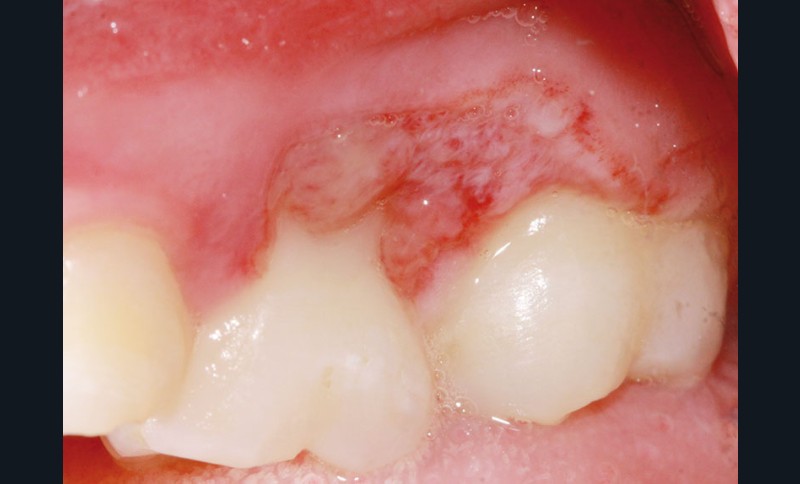

L’examen clinique révèle la présence d’une ulcération végétante, d’environ 1 cm de diamètre, localisée sur les gencives marginale, papillaire et attachée en vestibulaire de 55 et 16, associée à une récession parodontale pour 55. L’ulcération est bien délimitée, indolore et non hémorragique spontanément. Les dents présentent une mobilité physiologique et il n’existe pas d’adénopathie.

L’hypothèse la plus probable est celle d’une blessure d’origine traumatique, même si la jeune patiente et son entourage n’ont aucun souvenir des circonstances d’apparition.

Lors du contrôle à une semaine, la situation clinique ne s’est pas améliorée et devant l’aspect…